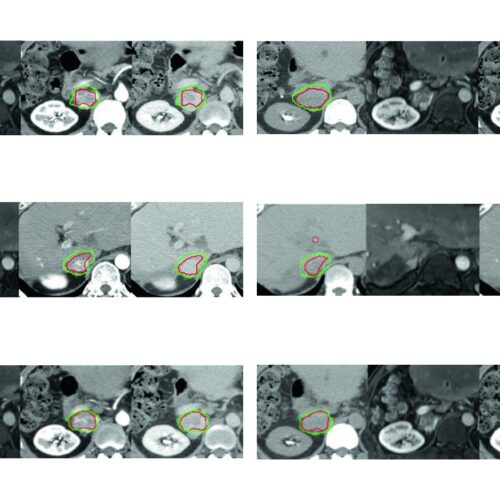

Delineamento de Volumes

Guias práticos de delineamento de volumes-alvo e órgãos de risco por sítio anatômico na radioterapia.